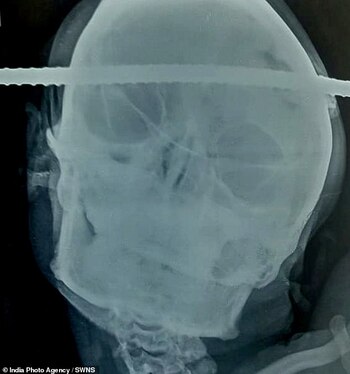

Las imágenes de Bahe tendido en la cama antes de la cirugía dieron la vuelta al mundo. Las fotos muestran la barra de hierro que atraviesa la región temporal derecha de su cerebro hasta la región frontal izquierda.

La barra fue extraída por un equipo de neurocirujanos tras una operación que duró noventa minutos en el Hospital Neuron. Pese a que la cirugía fue complicada por al estado crítico de presión arterial baja con el que ingresó Bahe, después de una hora y media, los médicos pudieron retirar la barra de manera segura y casi sin sangrado o lesión en el área circundante, informó el diario Daily Mail.

Según dijo el doctor Pramod Giri, el neurocirujano que dirigió la operación, los principales canales que conducen la sangre al cerebro de Bahe se salvaron apenas por milímetros.